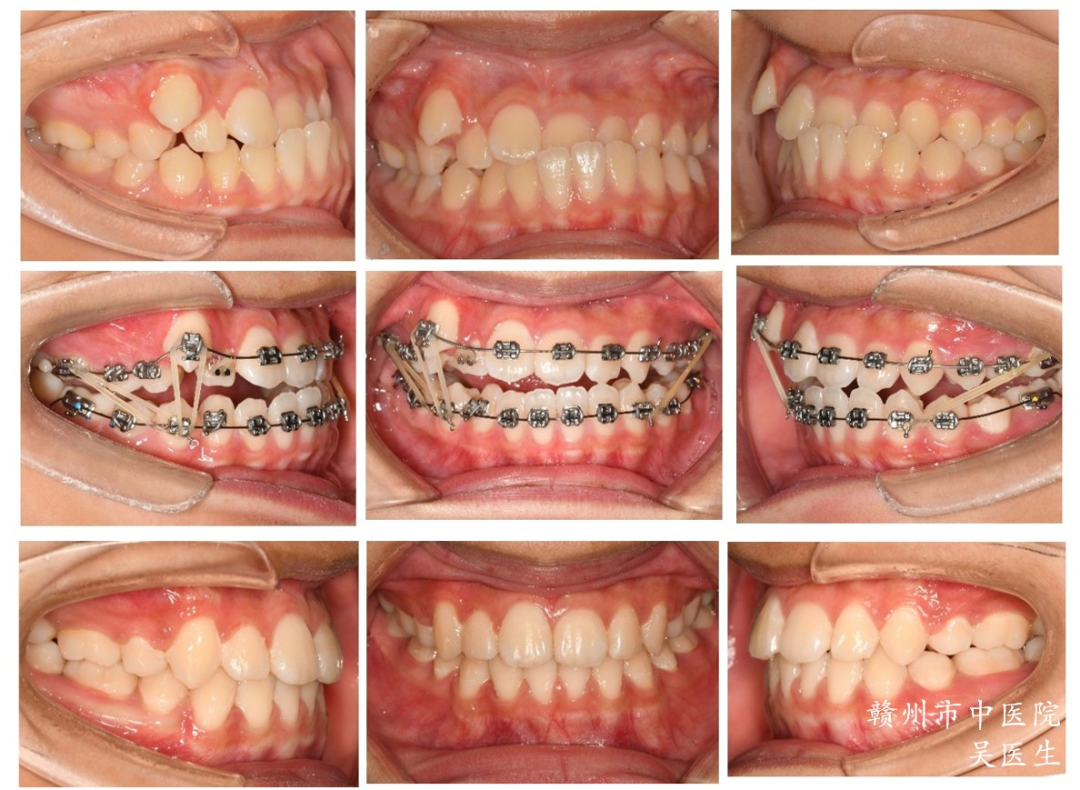

4.协助正畸治疗

CT检查可用于分析错牙合畸形中的骨性、牙性错牙合类型,可以通过测量角度、线距和比例等项目,判断被检者颅面及牙颌面的形态,判断咬合关系,可以用于指导正畸方案的制定,评估正畸效果。